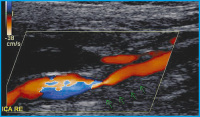

Extrakranielle ACI

Abbildung 3: Farbduplexsonographie der extrakraniellen ACI rechts: Darstellung einer langstreckigen zirkulären echoarmen Veränderung (Pfeile), einem intramuralen Hämatom entsprechend, die zu einer hämodynamisch relevanten Lumeneinengung führt. Befund der Kontrolluntersuchung einer 50jährigen Patientin, die mit einer rechtshirnigen TIA am Boden einer okklusiven Karotisdissektion symptomatisch wurde; Nachweis einer teilweisen Rekanalisation.

Keywords: ACIFarbduplexsonographieNeurologie